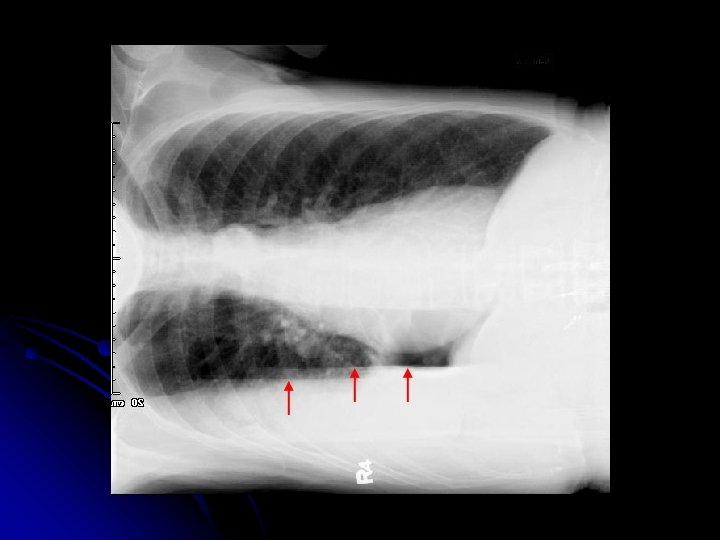

CÖ l 41 yaşında, işçi l Erkek l Doğum yeri: Gümüşhane l

l ŞİKAYETİ: Hemoptizi l 2006 şubat ayından beri tekrarlayan hemoptizi

l Özgeçmişi: Ø l 1997 - Tbc tanısıyla 6 ay tedavi Alışkanlıklar: Sigara 4 paket-yıl (7 yıldır içmiyor)

Balgamda Aside dirençli basil negatif l Kültürde M. Tuberculosis üremedi. l Orta sıklıkta PNL, az sayıda makrofaj l Atipik hücre görülmedi. l

l TORAKS BT (17/05/07): sol akciğer üst lob apikoposterior segment düzeyinde yaygın sekel fibrotik değişiklikler izlenmiştir. l BRONKOSKOPİ (22/02/07): Aktif kanama odağı saptanmadı

l Hastanın hemoptizilerinin tekrarlaması üzerine, hastaya 08/04/07 ve 11/05/07 tarihlerinde sol akciğer üst lob bronşial arterlerine embolizasyon uygulandı.

Ancak takiplerde hemoptizileri devam etti. l Kanama odağı? ? ? l

l Hastaya 07 -06 -2007’de sol akciğer üst lobektomi uygulandı. Lobektomi materyali patolojik inceleme için gönderildi.

l PATOLOJİ SONUCU: Sol Akciğer üst lobektomi materyali, kistik bronşiektazi, bu zeminde gelişmiş aspergilloma saptandı. l Hastaya İtraspor 100 mg tb 2 x 1 bir ay kullanmak üzere başlandı. itrakonazol